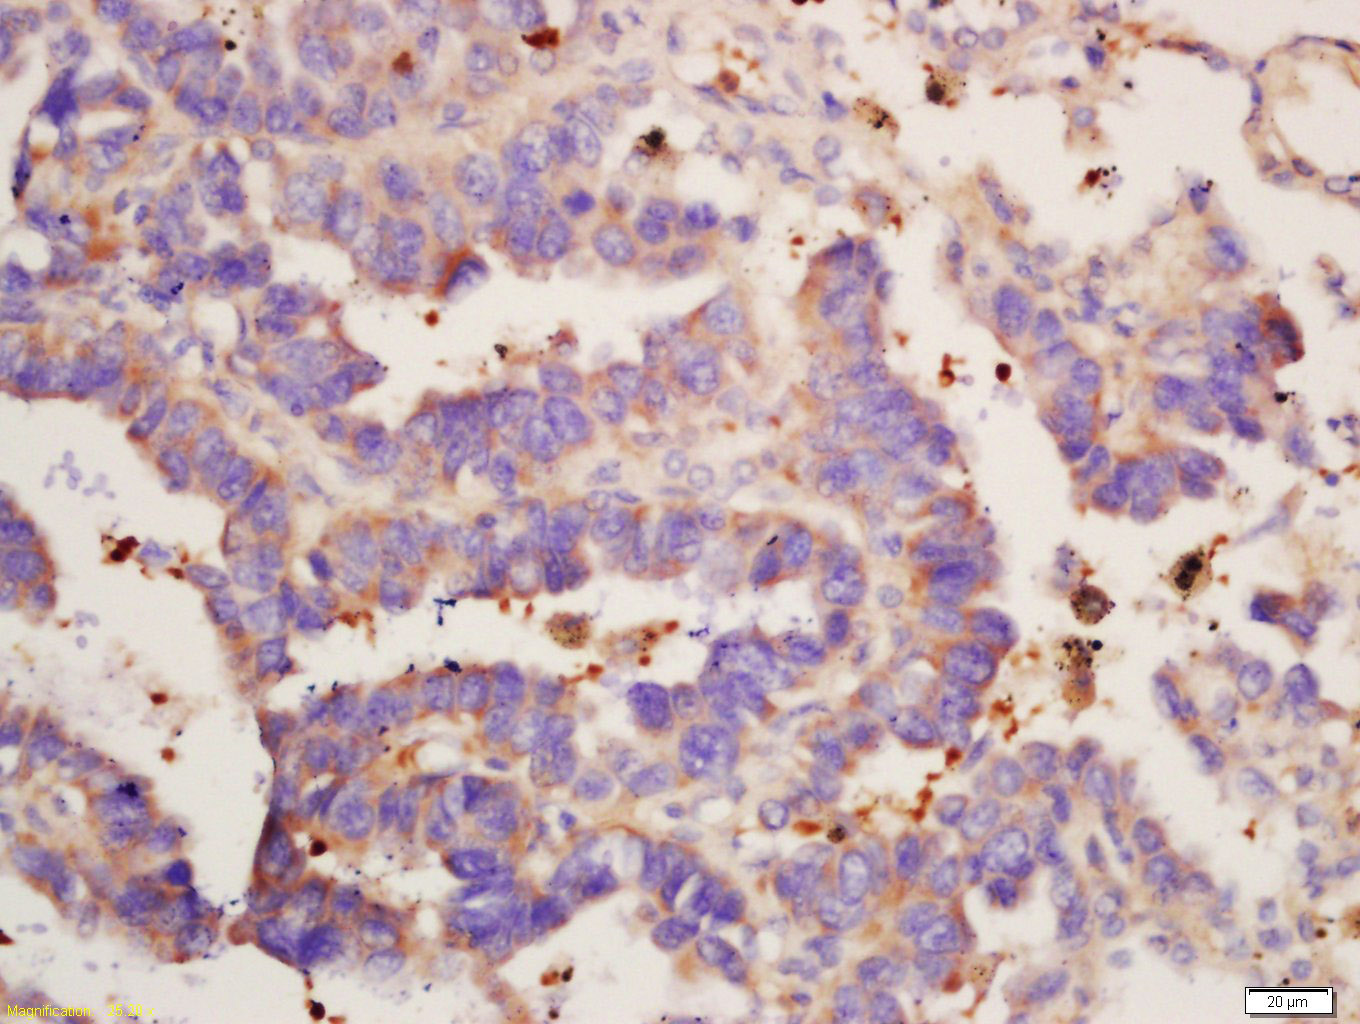

Tissue/cell: Human lung cancer tissue; 4% Paraformaldehyde-fixed and paraffin-embedded; Antigen retrieval: citrate buffer ( 0.01M, pH 6.0 ), Boiling bathing for 15min; Block endogenous peroxidase by 3% Hydrogen peroxide for 30min; Blocking buffer (normal goat serum,C-0005) at 37℃ for 20 min; Incubation: Anti-IL-12 beta Polyclonal Antibody, Unconjugated(bs-10777R) 1:200, overnight at 4°C, followed by conjugation to the secondary antibody(SP-0023) and DAB(C-0010) staining

Tissue/cell: human lung carcinoma; 4% Paraformaldehyde-fixed and paraffin-embedded; Antigen retrieval: citrate buffer ( 0.01M, pH 6.0 ), Boiling bathing for 15min; Block endogenous peroxidase by 3% Hydrogen peroxide for 30min; Blocking buffer (normal goat serum,C-0005) at 37℃ for 20 min; Incubation: Anti-IL-12 beta Polyclonal Antibody, Unconjugated(bs-10777R) 1:200, overnight at 4°C, followed by conjugation to the secondary antibody(SP-0023) and DAB(C-0010) staining